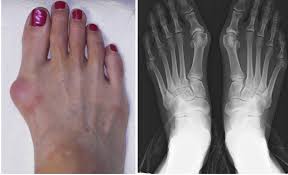

Čukljevi – sami po sebi su naslage soli. Njihovom formiranju doprinose: gripa, angina, giht, loš metabolizam, pogrešna ishrana, reumatske infekcije i dugo nošenje neudobne obuće.

Čukljevi na nogama su prava „noćna mora“ za ljude: veoma je teško pronaći odgovarajuću obuću, žuljaju, smetaju, bole i pored svega toga – daju vrlo ružan izgled noge.